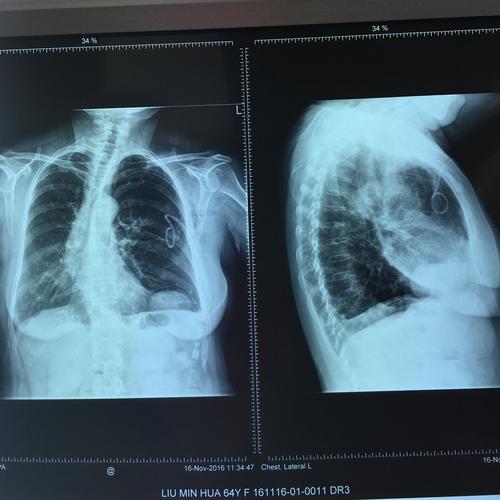

胸 片 正常 左侧胸腔积液 右侧气胸

引流2天后无气体引流出,行胸片观察肺复张情况 鉴于患者气胸反复发作